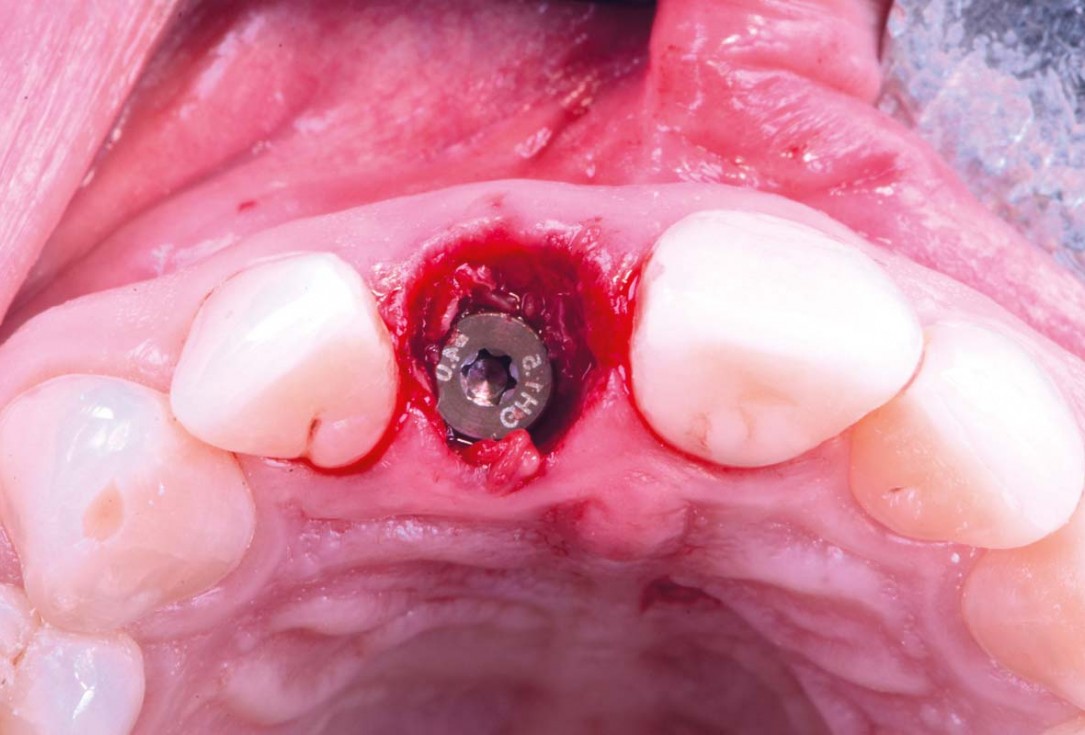

09/30 - Flapless implant placementExcellent aesthetic result of buccal augmentation with mucoderm® and maxgraft® after immediate implant placement - 3-years follow-up - Dr. A. Puišys

10/30 - Occlusal view – 4 mm placement depthExcellent aesthetic result of buccal augmentation with mucoderm® and maxgraft® after immediate implant placement - 3-years follow-up - Dr. A. Puišys